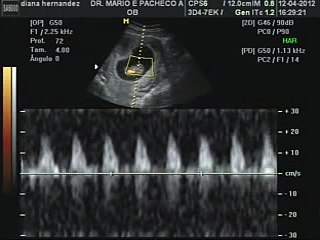

¿En qué ayuda un ultrasonido entre las semanas 11-13.6 del embarazo por un médico materno fetal?